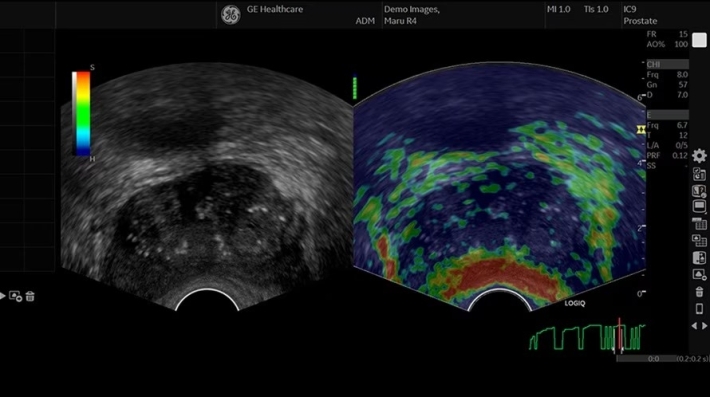

• IC9-RS — микроконвексный внутриполостной датчик;

• ShearWave Elastography — опция эластографии «сдвиговой волны»;

• Elastography Imaging Option — программа компрессионной эластографии;

• Q-analysis Option for Elastography and CF/PDI Quantification — программа количественного анализа для эластографии и анализа васкуляризации;